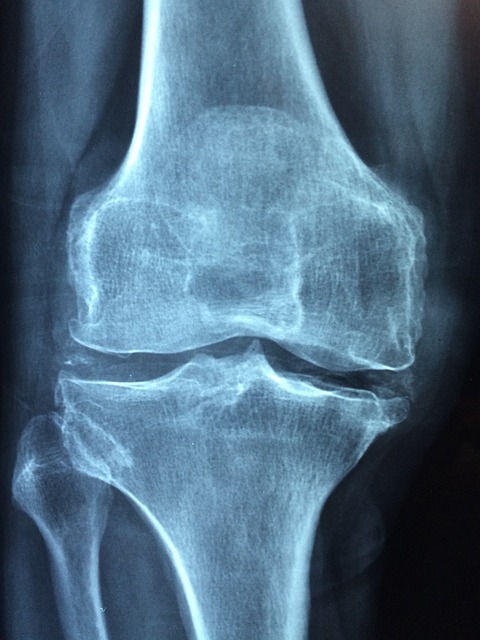

5. 무릎 통증 동반

고관절 문제는 무릎에도 영향을 미쳐 무릎에 통증을 유발할 수 있습니다. 이는 고관절과 무릎의 기능적 연관성 때문입니다.

10. 뻣뻣함 및 뚝뚝 소리

관절이 뻣뻣해지고 움직일 때 뚝뚝 소리가 난다면, 이는 관절 마찰이나 연골 손상의 신호일 수 있습니다. 이러한 증상은 초기에는 무시되기 쉽지만, 점차 심각한 문제로 이어질 수 있습니다.